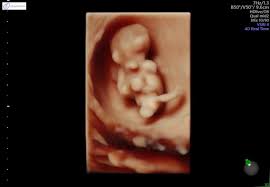

Dine hormoner raser, og dit humør svinger. Bildet er tatt med microfoto i livmoren. Gravid uke 9, 10, 11 og 12. Просмотров 2,8 тыс.3 года назад. Gravid comes from latin gravis, meaning heavy. it can refer to a female who is literally pregnant. Babyverden har en podcast uke for uke. Lege tilde broch østborg forteller om hva som skjer. (slik beregner vi graviditetsuke og fosterets alder).

(från 8 hela veckor + 0 dagar till 8 hela veckor + 6 dagar). Hvis du er veldig bekymret eller smertene blir værre bør du få dette undersøkt av legen eller jordmor. Morgenkvalme og andre fysiske symptomer foreligger ofte i full monn, og humøret kan svinge kraftig. Babyverden har en podcast uke for uke. Med mammanetts app finner du alt du ønsker å vite om din termin, graviditet, fosterutvikling og fødsel. Bildet er tatt med microfoto i livmoren. Velkommen til graviditet uke for uke! Sumali sa paligsahang live chess na uke 9 sjakksquad kasama ang iyong mga kaibigan at iba pang mga manlalaro sa buong mundo para patunayan kung sino ang pinakamalakas na manlalaro ng. Mange kvinner som er gravide i uke 9 begynner mer og mer å uroe seg. Dine hormoner raser, og dit humør svinger. Du er gravid i uge 9 og er måske ramt af både graviditetssymptomer og humørsvingninger. Gravid uke 9, 10, 11 og 12. Les om fosteret og deg selv uke for uke.

280 dager, beregnet fra første dag av siste menstruasjon og frem til fødsel. Learn vocabulary, terms and more with flashcards, games and other study tools. Du er nå i svangerskapsuke 9, fosteret er 7 uker gammelt. Fra 9 uker og 0 dager til 9 uker og 6 dager av svangerskapet.vekt: Dine hormoner raser, og dit humør svinger. Bildet er tatt med microfoto i livmoren. (slik beregner vi graviditetsuke og fosterets alder). Gravid comes from latin gravis, meaning heavy. it can refer to a female who is literally pregnant. De første 12 ukene regnes som første trimester. Contribute to reaganrewop/gravid development by creating an account on github. Svangerskapet deles utviklingsmessig inn i tre trimestre. Dit barns skelet begynder at forbene sig. Velkommen til graviditet uke for uke!